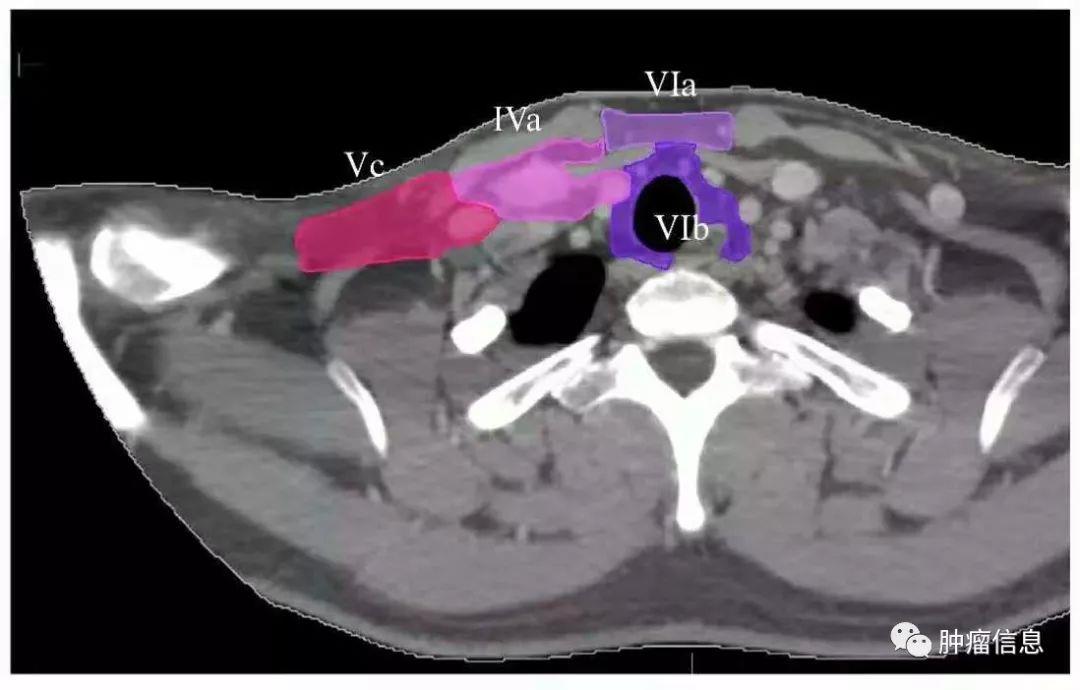

颈部VI区淋巴结

颈前淋巴结上界:舌骨下界:胸骨切迹后界:颈动脉鞘前方

颈部VI区图中紫色区域为VI区(VIa、VIb)

Ia:颏下淋巴组Ib:颌下淋巴组II:上颈淋巴组III :中颈淋巴组IVa:下颈淋巴组IVb:锁骨上内侧组V:颈后三角淋巴组Va:上颈后三角淋巴组Vb:下颈后三角淋巴组Vc:锁骨上外侧组VI:颈前淋巴组VIa:颈前淋巴结VIb:喉前、气管前、气管旁淋巴结VII:椎前淋巴组VIIa:咽后淋巴结VIIb:茎突后淋巴结VIII:腮腺淋巴组IX:面颊淋巴组X:颅底后组Xa:耳后、耳下淋巴结Xb:枕淋巴结见下图: